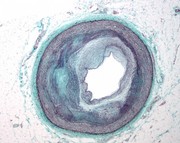

An international team which includes University of Manchester scientists has for the first time demonstrated that nerve signals are exchanged between clogged up arteries and the brain. The MRC-supported study of mice found that new nerve bundles are formed on the outer layer of where the artery is diseased, so the brain can detect where the damage is and communicate with it. |